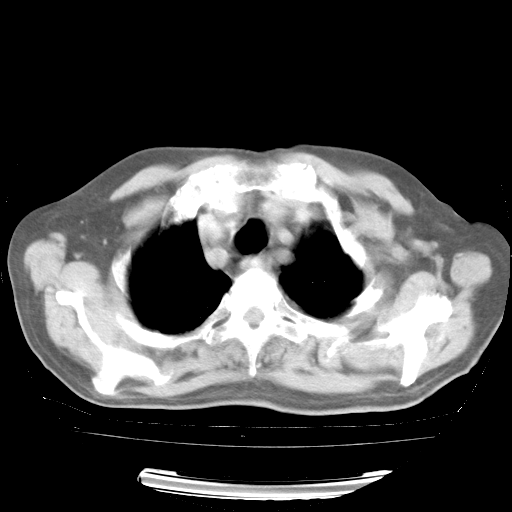

4月28日肺部CT——再次出现类似去年5月9日——透光度降低,“间质性”改变。

4月28日肺部CT——再次出现类似去年5月9日——磨玻璃样、间有“粟粒样”改变。